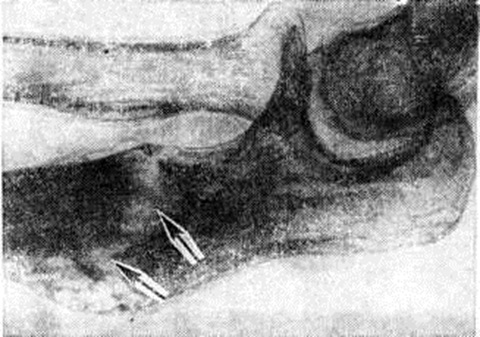

Наиболее выраженные изменения наблюдаются в костях локтевых суставов. В плечевых суставах деструктивные костные изменения менее выражены, чаще они проявляются частичной деструкцией головки плечевой кости и суставной впадины лопатки (рисунок 5). Обычно, несмотря на большие деструктивные костные изменения, остеопороз не отмечается.

Кроме остеоартропатий, при Сирингомиелия наблюдаются и остеопатии — трофические внесуставные изменения в диафизах длинных трубчатых костей, главным образом в костях предплечья, в виде локальных гиперостоза и рассасывания, приводящих к патологический переломам и образованию ложных суставов (рисунок 6). Так, иногда в локтевой кости наблюдаются зоны перестройки и остеолиза (рисунок 7), приводящие к нарушению целости кости и спонтанному перелому. Описаны своеобразные изменения скелета в виде увеличения костей кисти — так называемой хейромегалии.